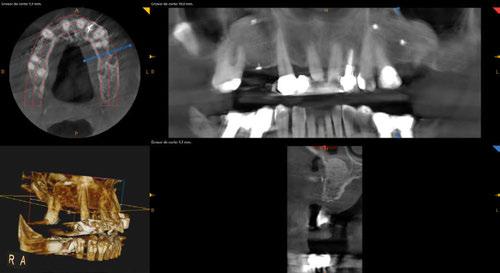

-CBCT para obtener imágenes en 3D del caso.

-Protocolo de planificación digital del caso mediante RealGUIDE® (STL+DICOM) (Figura 4) (Cuadro 1).

Figura 4. Planificación digital mediante RealGUIDE.

En la exploración radiográfica (OPG, CBCT) observamos la existencia de pérdida ósea interproximal, lesión apical a nivel de la raíz mesial del 27 y el cordal del primer cuadrante incluido y neumatización sinusal del primer y segundo cuadrante.

En el CBCT observamos pérdida ósea posterior superior debida a la neumatización de los senos maxilares izquierdo y derecho. También podemos observar disponibilidad ósea apical suficiente en dientes antero-superiores para la realización de una Implantología inmediata y corticales vestibulares y palatinas conservadas.